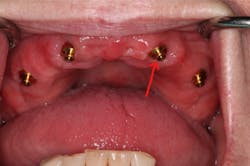

It is widely noted that a minimum of two implants are required in the mandible for removable dentures.5 Four or more implants are optimal for the maxilla.6 These minimums can be successful more than 85% of the time, but long-term success can be increased by adding additional implants (figure 4).7 Balaguer et al. studied 95 patients over an average of six to nine years and found that survival rate in the maxilla of four implants was 85.7%. Survival rate of six implants was 100%. In the mandible, survival rate of two implants was 96.6%, whereas survival rate for three implants was 100% and survival rate for four implants was 99%.7

Adding additional implants reduces stress on each individual implant. In most cases, it helps ensure that if an implant is lost, there will be enough remaining implants for a successful case. In the mandible, additional implants will increase retention and, therefore, patient satisfaction. We offer financial incentives for our patients to add additional implants. It’s a win-win. Our patients enjoy greater security and success, and we invest less clinical time on adjustments and addressing complications.